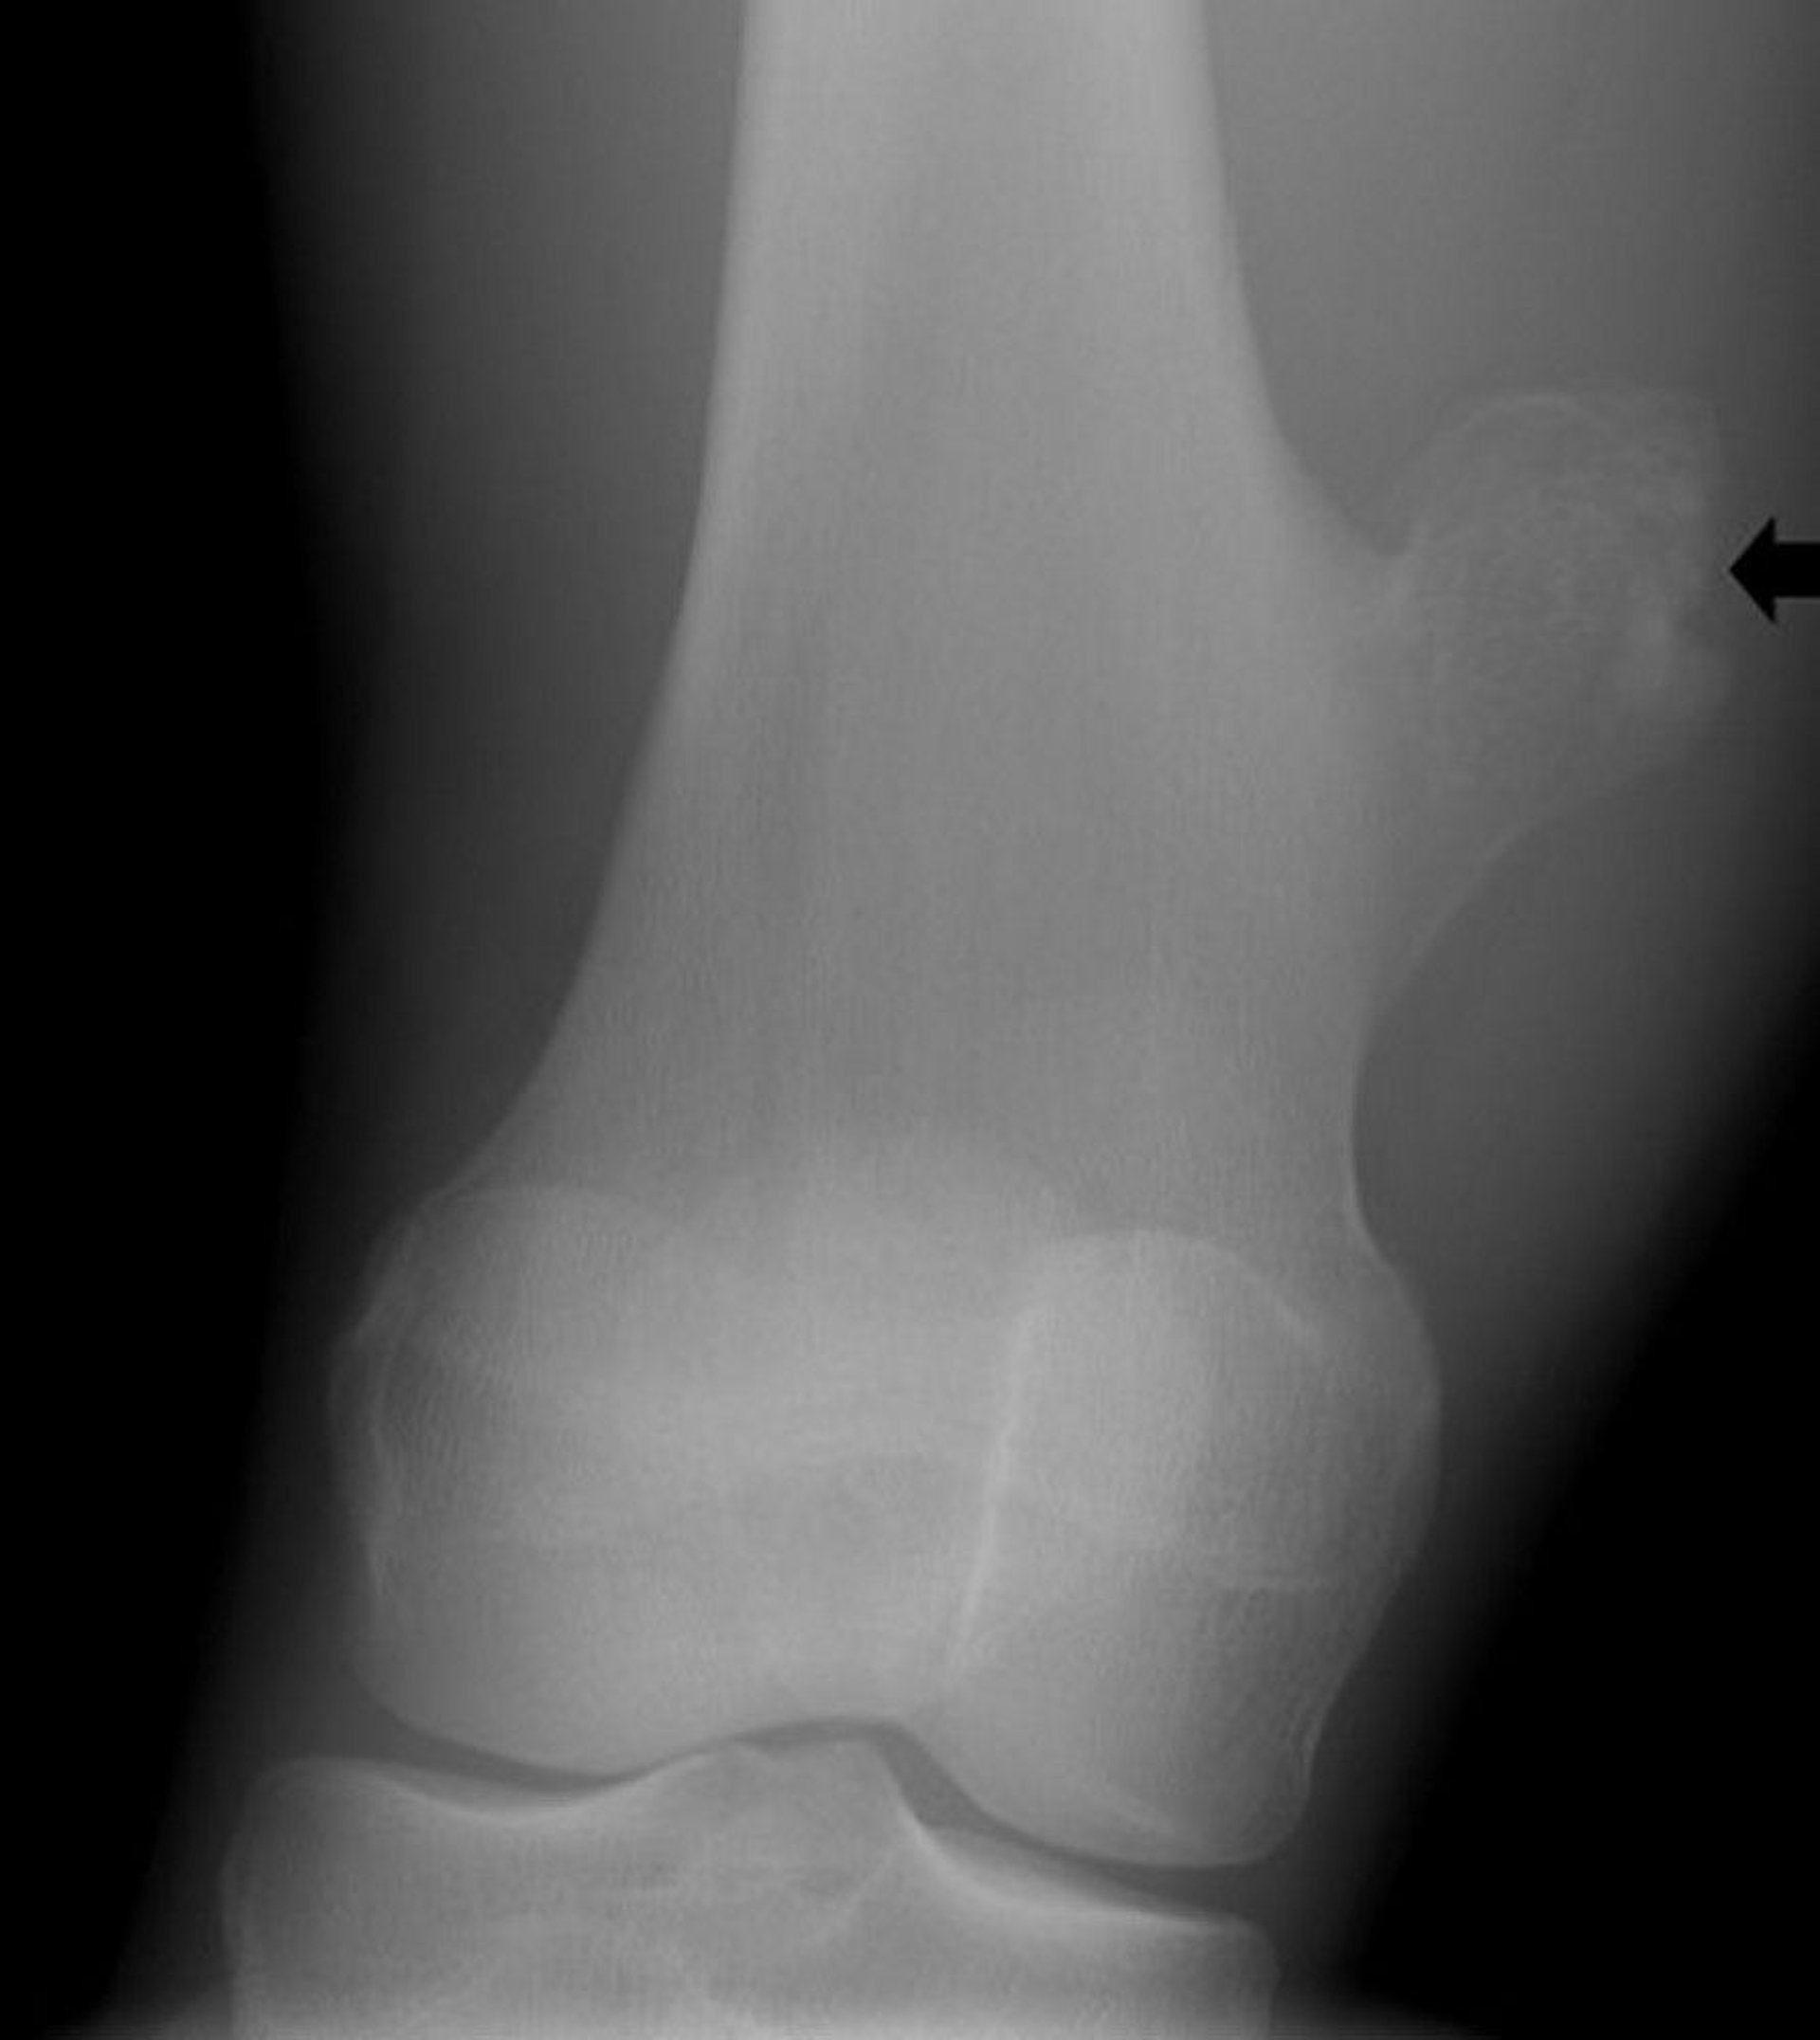

Osteochondroma of the Knee

This radiograph of the knee shows a bony outgrowth (arrow) from the femur above the knee joint that is consistent with an osteochondroma.

Image courtesy of Michael J. Joyce, MD, and Hakan Ilaslan, MD.